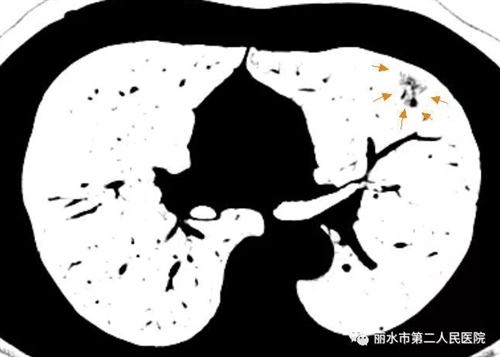

一般来说,肺内的良、恶性病变有时候均可以在肺部薄层CT影像上表现为磨玻璃结节,常见的原因可以是炎症、出血、不典型腺瘤样增生,当然也有可能是早期肺癌,包括原位癌、微浸润癌。

一般来讲,弥漫性生长的、边缘不清晰的、以纯磨玻璃表现为主的、短时间随访可消失的多数是良性病变;以局灶性生长为特征的、边缘清晰且伴有明显分叶、空泡、胸膜凹陷征、或病变内有明显实性成分的病变常提示恶性。